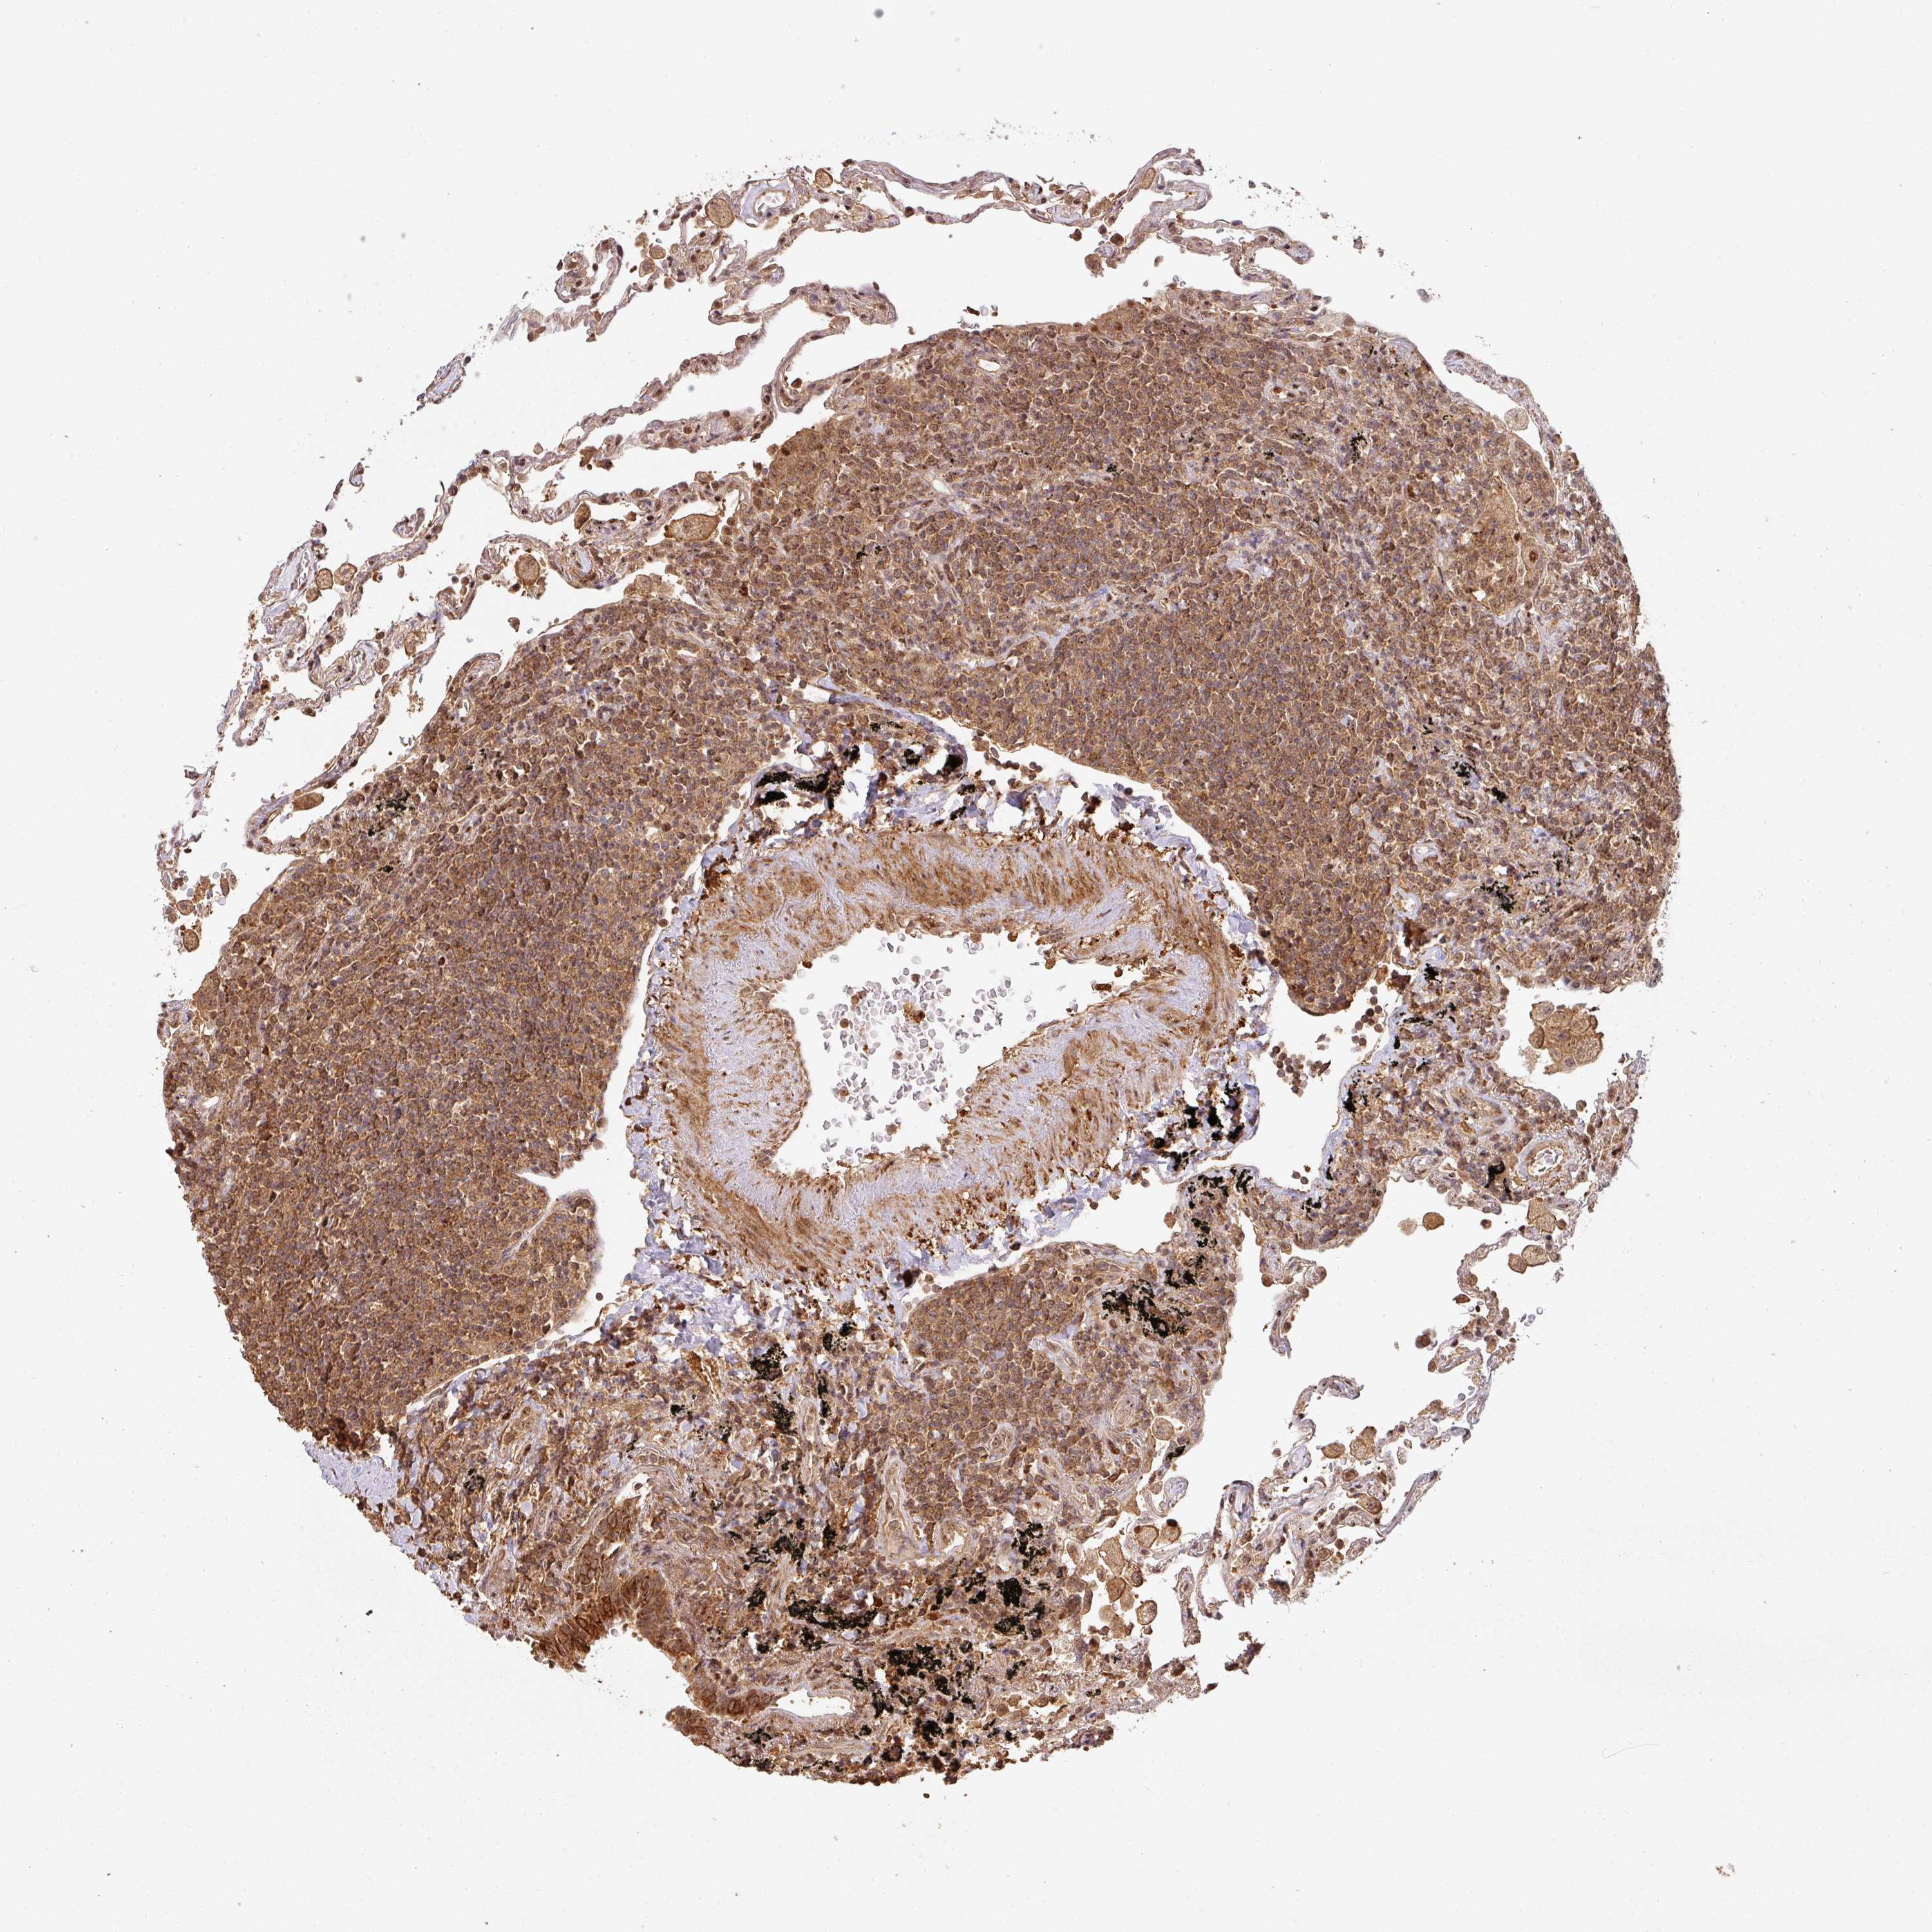

CANCER LYMPHOMA Show tissue menu

LYMPHOMA - Protein expressioni

A mouse-over function shows sample information and annotation data. Click on an image to view it in a full screen mode. Samples can be filtered based on level of antibody staining by selecting one or several of the following categories: high, medium, low and not detected. The assay and annotation is described here.

Each image is clickable and will lead to virtual microscopy that enables deeper exploration of all samples and also displays staining intensity scores, fraction scores and subcellular localization as well as patient and tissue information for each sample.

Antibody HPA043161

Antibody HPA046692

Staining

High

Medium

Low

Not detected

Intensity

Strong

Moderate

Weak

Negative

Quantity

>75%

75%-25%

<25%

None

Location

Nuclear

Cytoplasmic/membranous

Cytoplasmic/membranous,nuclear

Malignant lymphoma, non-Hodgkin's type, Low grade

Malignant lymphoma, non-Hodgkin's type, High grade

Hodgkin's disease, NOS